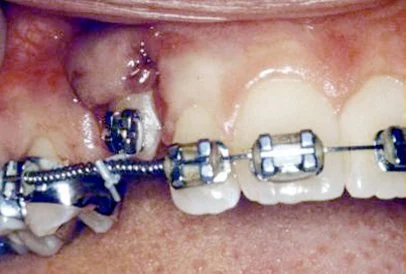

In a simple surgical procedure performed in the surgeon’s office, the gum on top of the impacted tooth will be lifted up to expose the hidden tooth underneath. If there is a baby tooth present, it will be removed at the same time. Once the tooth is exposed, the oral surgeon will bond an orthodontic bracket to the exposed tooth. The bracket will have a miniature gold chain attached to it. The oral surgeon will guide the chain back to the orthodontic arch wire where it will be temporarily attached. Sometimes the surgeon will leave the exposed impacted tooth completely uncovered by suturing the gum up high above the tooth or making a window in the gum covering the tooth (on selected cases located on the roof of the mouth). Most of the time, the gum will be returned to its original location and sutured back with only the chain remaining visible as it exits a small hole in the gum.

Shortly after surgery (same day-14 days) the patient will return to the orthodontist. A rubber band will be attached to the chain to put a light eruptive pulling force on the impacted tooth. This will begin the process of moving the tooth into its proper place in the dental arch. This is a carefully controlled, slow process that may take up to a full year to complete. Remember, the goal is to erupt the impacted tooth and not to extract it! Once the tooth is moved into the arch in its final position, the gum around it will be evaluated to make sure it is sufficiently strong and healthy to last for a lifetime of chewing and tooth brushing. In some circumstances, especially those where the tooth had to be moved a long distance, there may be some minor “gum surgery” required to add bulk to the gum tissue over the relocated tooth so it remains healthy during normal function. Your dentist or orthodontist will explain this situation to you if it applies to your specific situation.

You can expect a limited amount of bleeding from the surgical sites after surgery. Although there will be some discomfort after surgery at the surgical sites, most patients find Tylenol or Advil to be more than adequate to manage any pain they may have. Within two to three days after surgery there is usually little need for any medication at all. There may be some swelling from holding the lip up to visualize the surgical site; it can be minimized by applying ice packs to the lip for the afternoon after surgery.

Bruising is not a common finding at all after these cases. A soft, bland diet is recommended at first, but you may resume your normal diet as soon as you feel comfortable chewing. It is advised that you avoid sharp food items like crackers and chips as they will irritate the surgical site if they jab the wound during initial healing. Your doctor will see you seven days after surgery to evaluate the healing process and make sure you are maintaining good oral hygiene. You should plan to see your orthodontist within the same day to 14 days post surgery to activate the eruption process by applying the proper rubber band to the chain on your tooth. As always your doctor is available at the office or called after hours if any problems should arise after surgery. Simply call us if you have any questions.